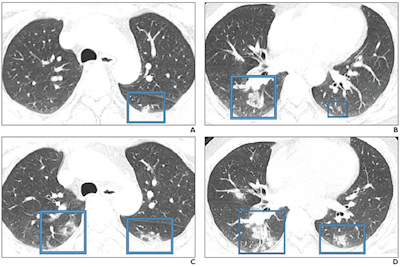

"An investigation of initial chest CT findings in 21 individuals with confirmed COVID-19 reported abnormal findings in 86% of patients, with a majority having bilateral lung involvement," the authors wrote.

"Although the imaging features [of COVID-19] closely resemble those of MERS and SARS, involvement of both lungs on initial imaging is more likely to be seen with COVID-19," the group wrote. "Initial chest imaging abnormalities in SARS and MERS are more frequently unilateral."

The three diseases share the following symptoms: fever, dyspnea, malaise, myalgia, and headache; all three also tend to show ground-glass opacity, consolidation, or both on imaging, while lymphadenopathy is not usually seen. Clinicians have been diagnosing COVID-19 in patients with these symptoms who recently traveled to China.

- COVID-19: Consolidation (versus ground-glass opacity)